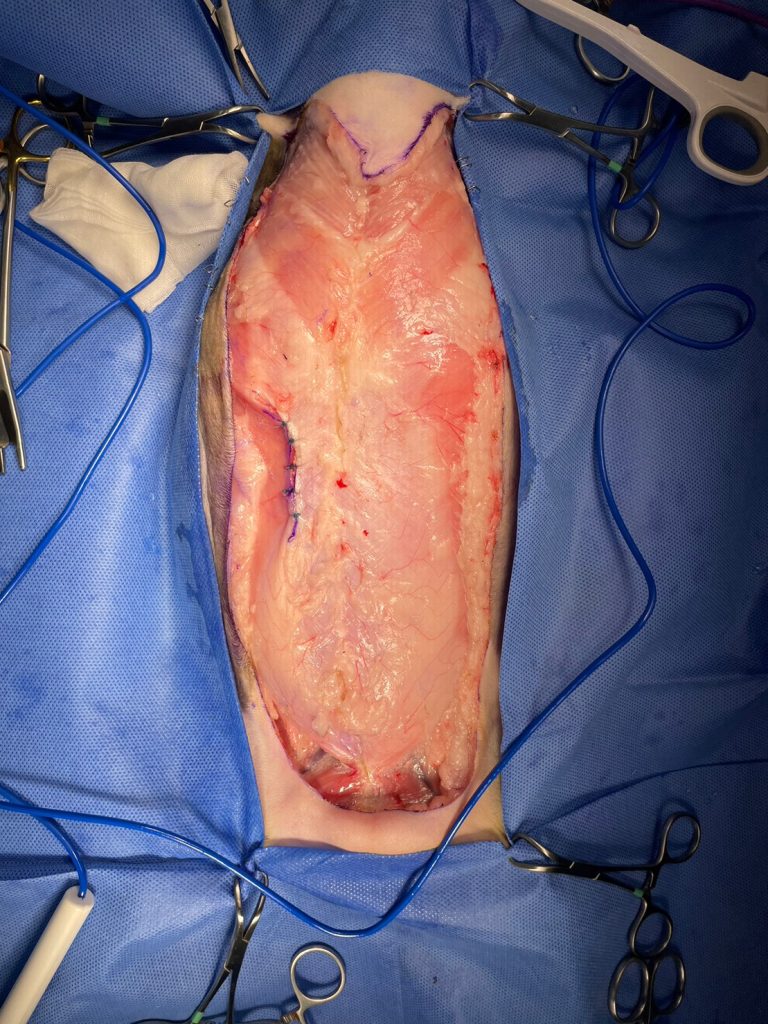

如同這張圖,左側乳腺以及淋巴結都已切除乾淨,幾乎看不見有地方在出血。

最後,我們將創口關閉,張力並不會太大,這表示術後貓應該會恢復得蠻順利的。